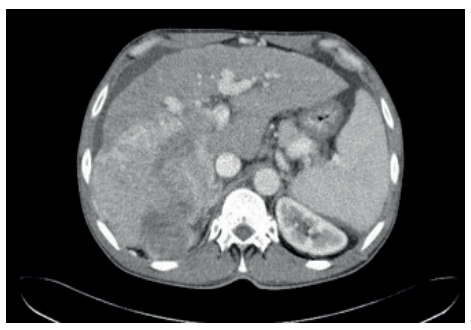

Estágio B (Intermediário)

Pacientes com múltiplos nódulos, mas sem invasão vascular, Child A/B.

- Conduta: Quimioembolização Transarterial (TACE).

- Mecanismo: Injeta-se quimioterápico diretamente na artéria que nutre o tumor e, em seguida, oclui-se o vaso (embolização). O tumor sofre por ação da droga e por isquemia.

Terapias Locorregionais (Estádio B – Intermediário)

Para o paciente com doença multinodular, mas restrita ao fígado e com função preservada.

Quimioembolização Transarterial (TACE)

- Mecanismo: Cateterismo superseletivo da artéria hepática que nutre o tumor. Injeta-se quimioterápico + partículas embolizantes. O tumor sofre por isquemia (corta o suprimento) e citotoxicidade (droga local).

- Resultados: Aumenta a sobrevida mediana para > 26-30 meses.

- Contraindicações: Trombose de veia porta (pois o fluxo portal é o que mantém o fígado não tumoral vivo após a embolização arterial) e descompensação hepática (Child C).